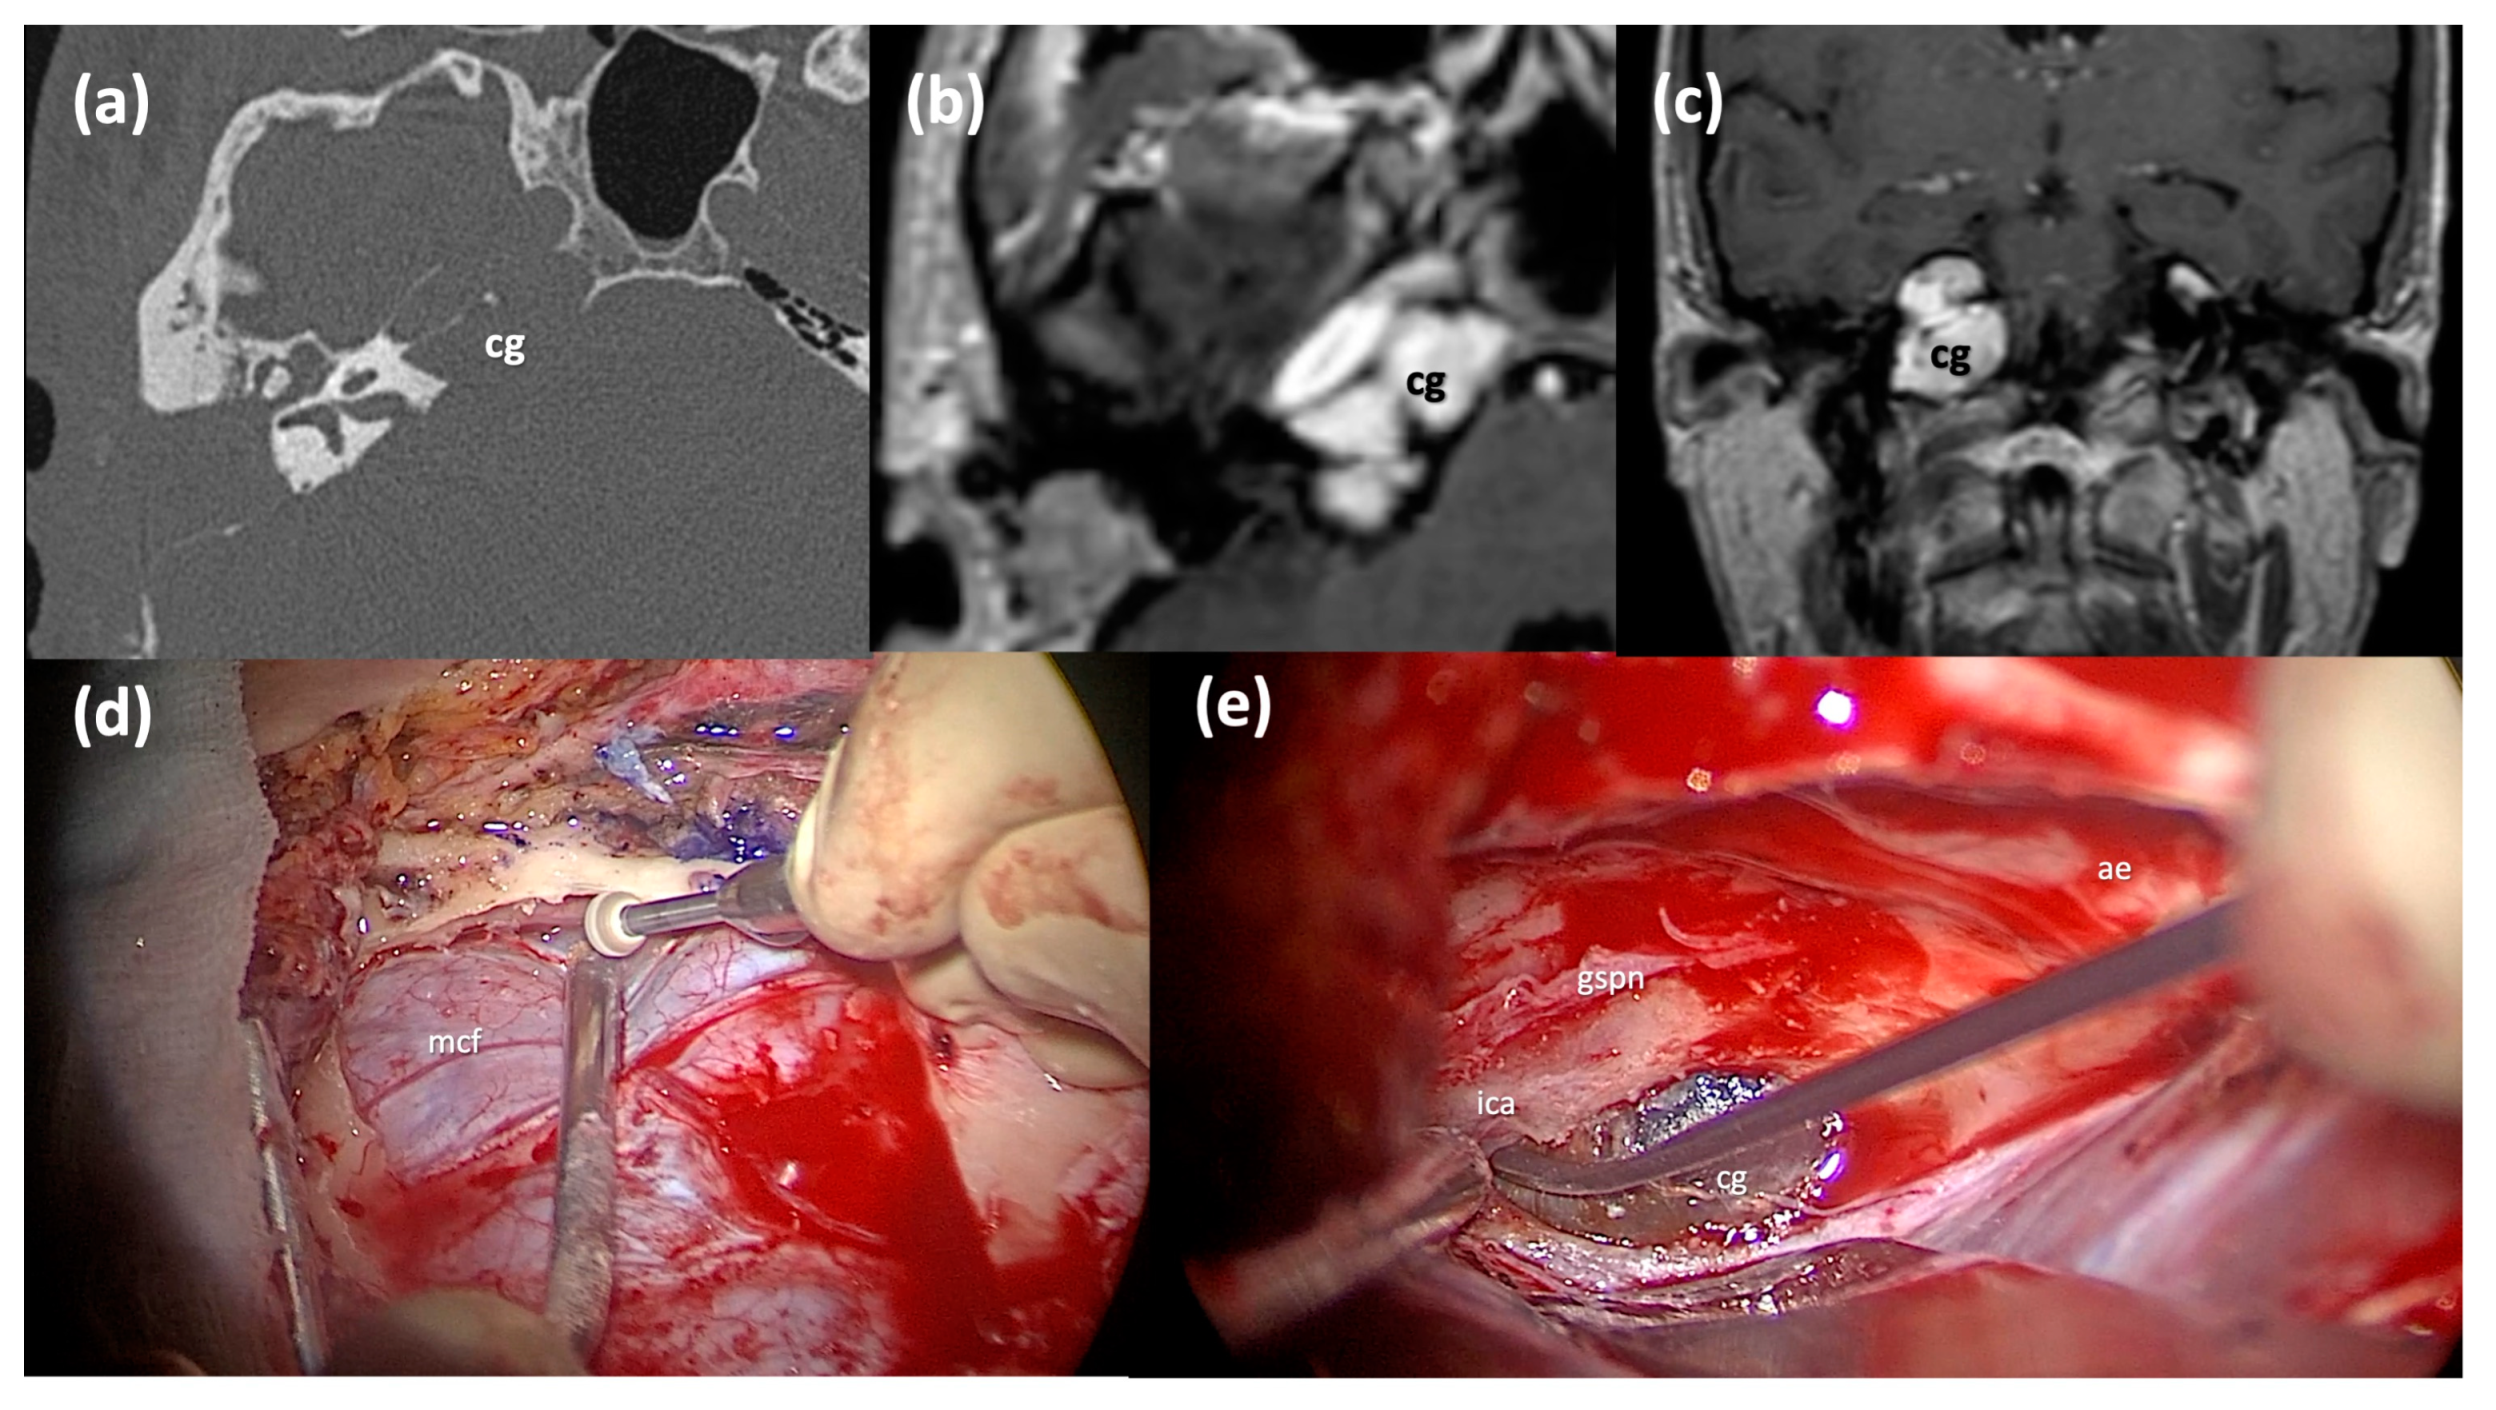

On the other hand, for what concerns the middle cranial fossa approach, this is chosen for patients for whom a fenestration is not possible due to unfavorable anatomical conditions, with a preoperative normal hearing function or a serviceable hearing. It is usually proposed for cholesterol granulomas that extend into the middle fossa, medial to the ICA [15]. This surgical route often allows the pseudo-capsule to be completely removed; however, it is very difficult to achieve a stable aeration of the cavity, which must be obliterated. In some cases, a drainage route can be created through the tegmen tympani. The middle cranial fossa approach is based on a temporal craniotomy (4 × 4 cm) above the zygomatic process, the subsequent exposure of the middle cranial fossa dura and the elevation of the temporal lobe from the floor of the middle cranial fossa. The greater superficial petrosal nerve and the horizontal tract of the underlying intrapetrous ICA are identified at the level of the petrous apex. In the posterior portion of the field the IAC is identified while anteriorly the middle meningeal artery is coagulated and severed. The mandibular branch of the trigeminal nerve within the foramen ovale is identified as the anterior limit of the approach. Finally, after the elevation of the dura of the middle fossa, the petrous apex bone between the above-mentioned identified structures (Kawase triangle) is drilled to reach the cholesterol granuloma, which is subsequently removed (Figure 5).

Figure 5.

Middle cranial fossa approach. (a) Axial CT scan of a right Type C PACG with erosion of the horizontal ICA bone walls. (b,c) Axial and Coronal T1-weighted MRI sections of the same PACG, showing the typical hyperintense signal. (d) Surgical step: a craniotomy has been performed and the dura of the middle cranial fossa is carefully elevated from the skull base. (e) Surgical step: the lesion is identified after the Kawase triangle drilling. cg: cholesterol granuloma; mcf, middle fossa dura; gspn, greater superficial petrosal nerve; ae, arcuate eminence; ica, internal carotid artery.

In the majority of cases treated with this approach, it is difficult to create a drainage fenestration of the cholesterol granuloma cavity towards the mastoid or tympanic or sphenoidal sinus spaces. Even the total removal of the cysts is not always possible, especially if the granuloma develops well underneath and lateral to the horizontal portion of the ICA. The implementation of the endoscope in combination with the microscopic technique has allowed for the optimization of the removal of the granuloma through this approach. However, in most cases, residues of the pseudo-capsule may remain. Therefore, when a proper drainage corridor is not easily achievable, a middle cranial fossa approach can be used to perform a subtotal resection, leaving part of the cystic content behind, or a near-total resection, leaving only part of the pseudo-capsule in the surgical cavity. In all these cases, a follow-up is necessary over the years for a possible recurrence of the cholesterol granuloma formation or when symptoms reappear.